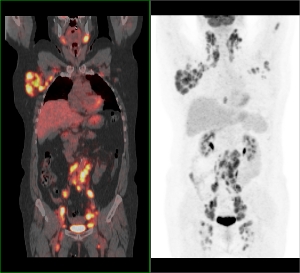

PET/CT vyšetrenie trupu s 18F-FDG

Široká škála onkologických aj neonkologických indikácií